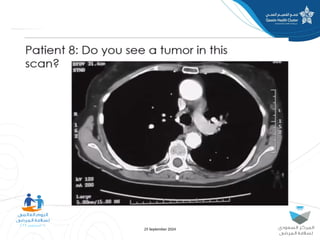

The document discusses diagnostic errors, particularly focusing on cognitive biases and their impact on decision-making in healthcare. Dr. Asmaa Fayez emphasizes the importance of recognizing and mitigating these biases to avoid human errors that can lead to serious incidents. The presentation highlights the urgent need for timely interventions in the context of patient safety.